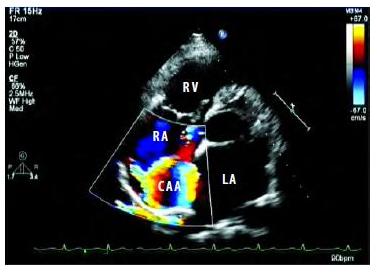

4、多普勒成像

D型超声成像系统:又称频移诊断法,即接收频率与发射频率之差,又称多普勒频移。目前可分为脉冲式多普勒、连续式多普勒、高脉冲重复频率式多普勒、多点选通式多普勒以及彩色多普勒血流显像五种。